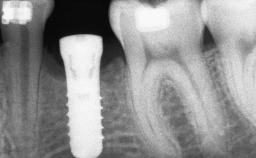

A 47-year-old Caucasian woman with a single-tooth edentulous space at the site of the left maxillary canine was referred for treatment. She had undergone traumatic extraction of this impacted canine several months before referral. Her chief complaint was the dissatisfying appearance of her smile. The patient desired a stable and esthetic rehabilitation of the site. Her dental history showed no evidence of periodontal disease or bruxism. She had no systemic diseases, was not taking any medications, and did not smoke. The extraoral examination revealed a high lip line and an inadequate soft-tissue volume at the defective canine site. Large black triangles were visible between the canine and its adjacent teeth.

# of Implants 1

Type of Implants Two-Piece

Bone Augmentation Staged|Vertical

Placement Protocol Early or late implant placement